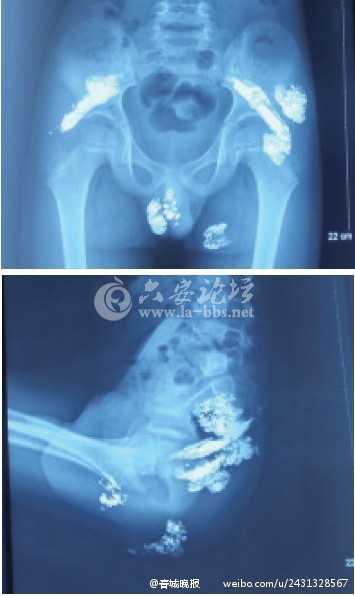

江女士介绍,今年年初发现孩子身上起脓包,还以为是普通皮肤病,了解病情后,带着孩子四处诊治无果,甚至曾一度绝望。

奇奇60多岁的爷爷于迪(化名)介绍,大约两年前,他和老伴发现孙子排出的粪便里有水银,之后带奇奇去昆明市儿童医院检查,医生说,水银已通过粪便排出了孩子体外,没事了。

去年11月,家人发现奇奇臀部左右两侧各起了两个大包,于迪用手指圈起来一个一元硬币大小的圈,“肿起来一两厘米高。”

于迪说,孙子刚开始不怎么喊痛,后来肿块越来越大,痛得坐不住,玩电脑都是跪着。

直到今年二月份,儿子和儿媳妇挤破这些肿块,发现里面流出来的不是脓血,而是亮晶晶的水银。

家人带着孩子辗转求医,最后送入北京解放军307医院治疗。

今年2月,昆明男童奇奇(化名)体内被检出汞含量严重超标,其中血汞和尿汞含量分别超标200多倍和1万多倍。事件经曝光后,引起极大关注。昨天记者从昆明市公安局有关部门获悉,目前一名男性犯罪嫌疑人已被检察机关批捕,具体案情仍在进一步调查。